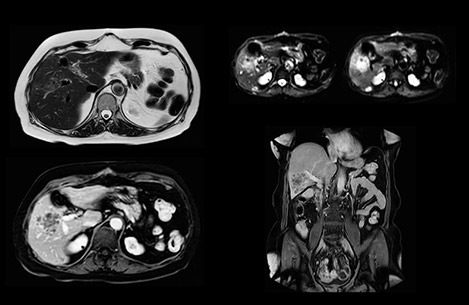

Comparison of liver MRI with and without MultiVane XD motion correction

In this example the image quality of the MultiVane XD images is evidently better than in the images without MultiVane XD. Ingenia 1.5T with dS Torso coil solution.

bremen case image comparison

“We acquire one transversal high resolution T2-weighted sequence with 3 mm slice thickness, for example for pancreas or liver lesions. Then we also add a T2 fat suppressed MultiVane XD SPIR sequence. We perform these two routinely in our liver imaging. We use high dS SENSE factors to significantly shorten scan times to 2-4 minutes, which can improve our protocol; it’s a very robust scan.”

“We include mDIXON for the dynamic sequences because of the robust and homogeneous fat suppression we get with that. We had been using eTHRIVE, but we are now quite happy with mDIXON. Sometimes we use a medication to calm the bowels, to further improve the image quality.”